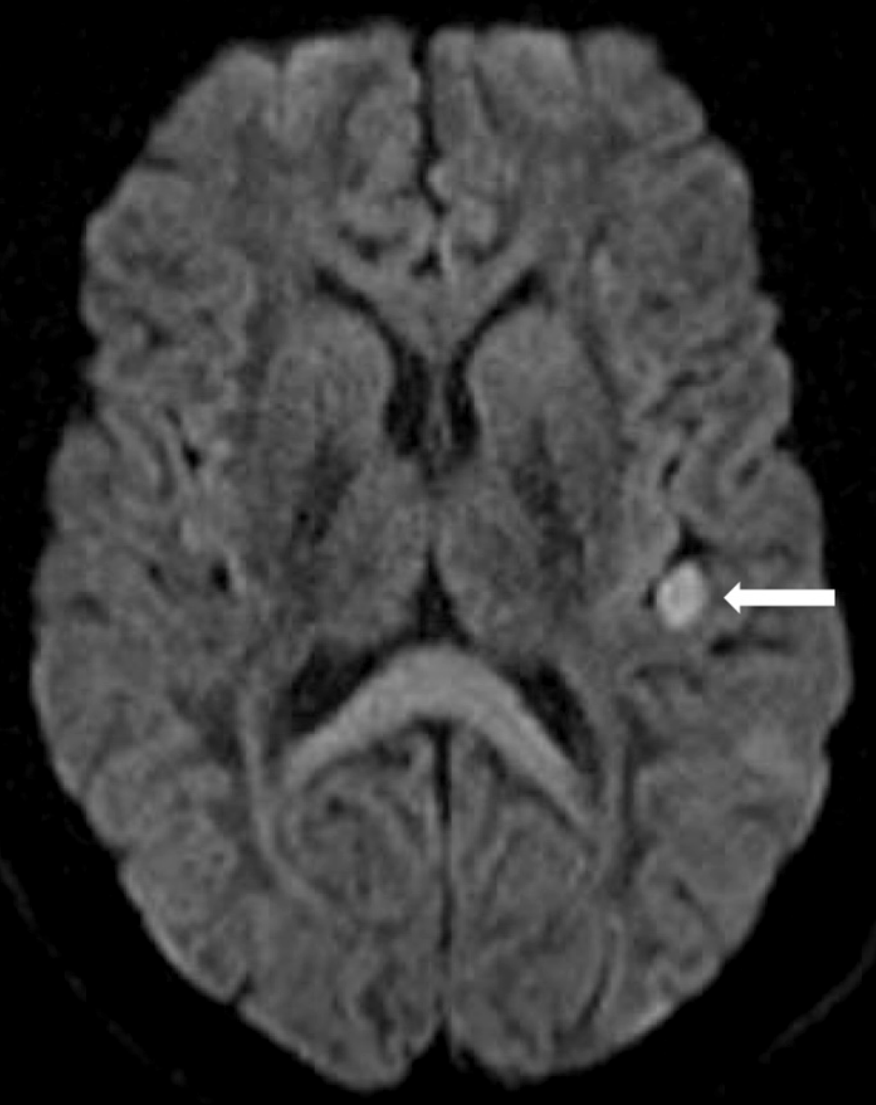

患者开始接受依诺肝素治疗。因头部外伤,行头颅CT(平扫)显示双额叶斑片状脑挫伤,无明显占位效应;进一步行脑MRI,显示左脑岛、颞上回及颞中回多发急性梗死灶,伴点状出血转化(图 2)。因担心加重颅内出血风险,停用依诺肝素。

图 2脑MRI示左脑岛皮层梗死灶(实心箭头)。